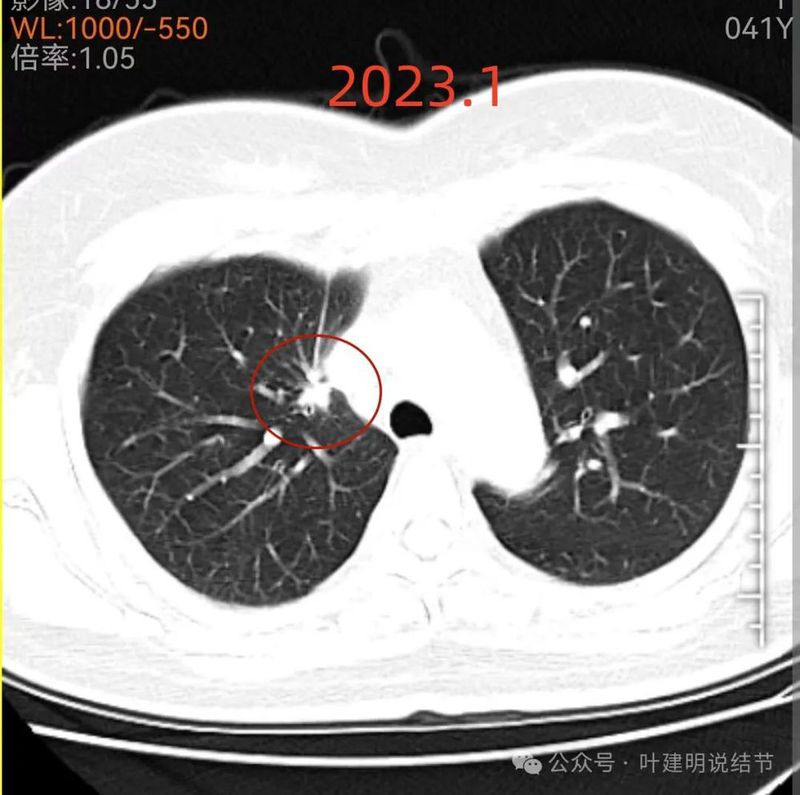

先看2023年1月时的影像:

右上叶贴着纵隔侧有实性结节,表面不平毛糙,有毛刺征,邻近细支气管扩张,纵隔胸膜略有牵拉,膨胀性不太明显。